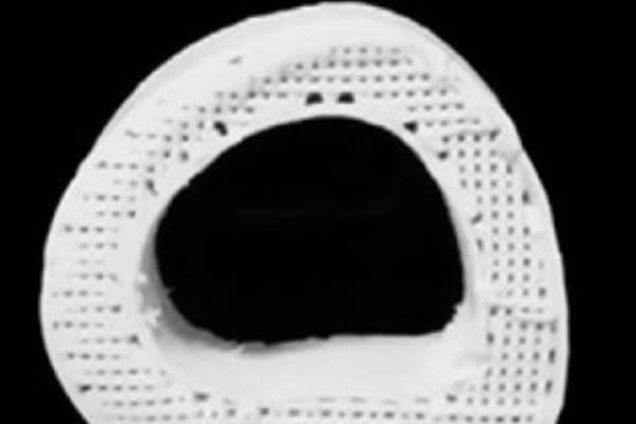

Но этот материал не только эластичен. Он еще и обладает высокой пористостью — микропустоты составляют до половины объема "искусственной кости". Это позволяет клеткам проникать во внутреннюю структуру материала. При этом появляются кровеносные сосуды и начинает расти настоящая костная ткань.

"Пористость очень важна, когда речь идет о регенерации тканей. Когда вы кладете стволовые клетки на наши каркасы, они превращаются в клетки кости и начинают регулировать развитие и рост кости", - говорит Рамиль Шах, который руководил исследованием.